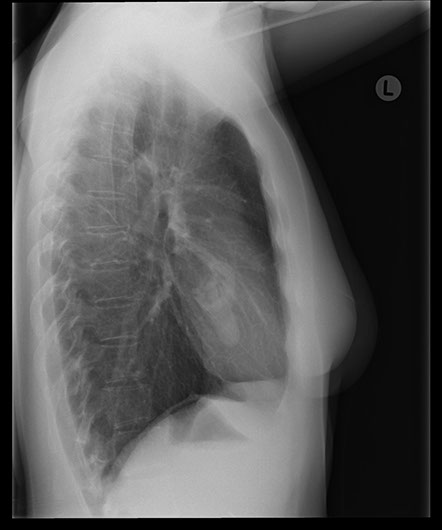

The cause of the stroke in this lady is most likely the arteriovenous malformation in the posterior parietal region, where multiple ectatic sections are present which drain into superior sagittal sinus. Thrombus may form in the dilations and lead to a stroke or they could be areas of haemorrhage. However, in this case, the arteriovenous malformations in the lungs could also have been the source of an embolus.

This turned out to be another AV malformation which was occluded by multiple coils. Note the post embolisation picture in the bottom right corner.